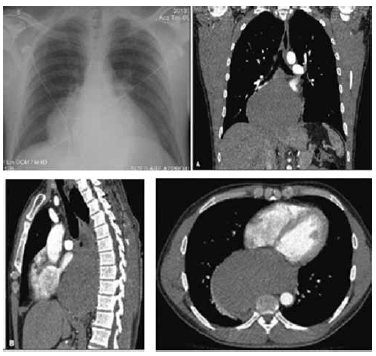

Homem de 40 anos foi hospitalizado para investigação de tosse seca e febre diária há 10 dias. O exame físico não mostrou alterações. Exames laboratoriais mostraram anemia normocítica, normocrômica (Hb = 9,7 g/dL), PCR elevada (PCR = 33,1 mg/dL), plaquetose (plaquetas = 592.000/mm3) e leucocitose sem desvio (leucócitos = 14.290/mm3). O paciente evoluiu com picos febris diários e taquicardia. Realizou RX tórax e Tomografia de Tórax (demonstrados a seguir).

A hipótese diagnóstica do paciente é: